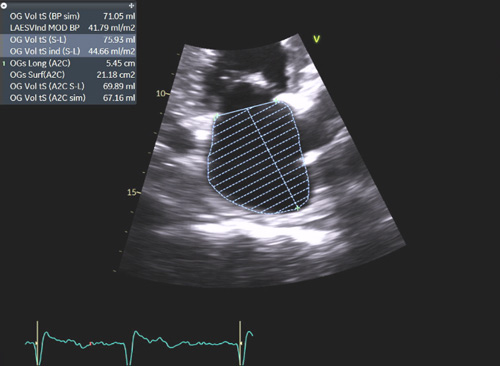

La dilatation des oreillettes est fréquente et s’associe à une dysfonction diastolique. Les pressions de remplissages VG sont souvent élevées (Figure 2) sauf à un stade préclinique chez certains patients a- ou peu symptomatiques. L’étude de la fonction diastolique ventriculaire gauche est basée sur une approche multiparamétrique intégrant le Doppler pulsé mitral, le DTI à l’anneau mitral, le volume de l’oreillette gauche (>32-34 ml/m² SC) et la Vmax du flux d’IT (>2.8 m/s) permettant également d’estimer les pressions artérielles pulmonaires (PAPS).

Figure 2 : Pressions de remplissage VG élevées souvent élevées en cas d’amylose cardiaque évolutive.

Exemple de pressions de remplissages élevées chez un patient avec amylose cardiaque : E/A >2, E/E’ moyen = 13, volume biplan indexé de l’OG > 34 ml/m² SC, Vmax de l’IT proche de 2.8 m/s